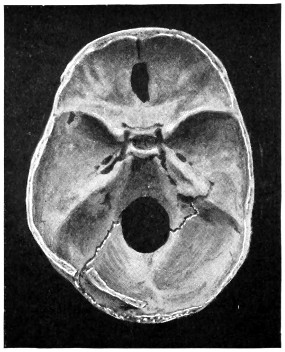

| 50 A and B. The inner aspect of the skull and the same seen on transillumination | 137 |

| 51. To illustrate compression of the brain as produced by an extra-dural hæmorrhage from the middle meningeal artery[x] | 141 |

| 52 A and B. The operative treatment of middle meningeal hæmorrhage | 144, 145 |

| 53. A basic fracture with laceration of both carotid arteries | 148 |

| 54. A basic fracture with laceration of the cavernous sinus | 149 |

| 55. A basic fracture with laceration of both lateral sinuses | 151 |